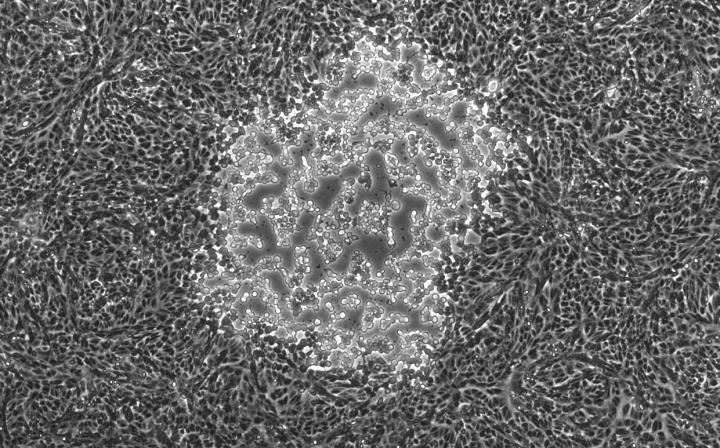

The genomes of two distinct strains of the virus that causes the common lip cold sore, herpes simplex virus type 1 (HSV-1), have been identified within an individual person -- an achievement that could be useful to forensic scientists for tracing a person's history. The research also opens the door to understanding how a patient's viruses influence the course of disease. The research by an international team led by Moriah L. Szpara, assistant professor of biochemistry and molecular biology at Penn State University, will be published in the May 2016 issue of the journal Virology .

Most people harbor HSV-1, frequently as a strain acquired from their mothers shortly after birth and carried for the rest of their lives. The new discovery was made with the help of a volunteer from the United States. The research revealed that one strain of the HSV-1 virus harbored by this individual is of a European/North American variety and the other is an Asian variety -- likely acquired during the volunteer's military service in the Korean War in the 1950s.